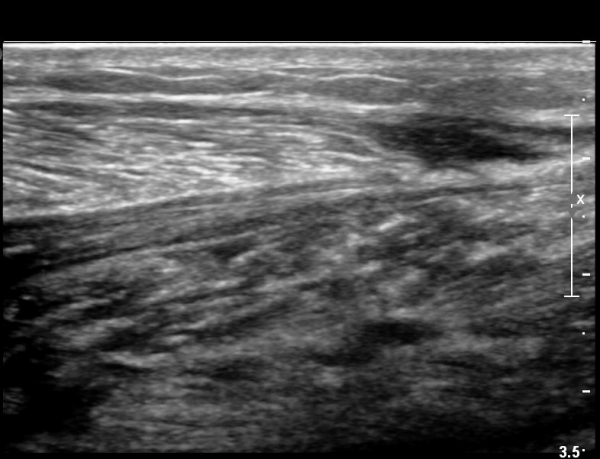

2018³â  1¿ù 30ÀÏ ÃßÀû°Ë»ç

¾ÆÅ³·¹½º°Ç Àú¿¡ÄÚºÎÁ¾ÀÌ °¨¼ÒµÇ°í  ÆÄ¿­ºÎÀ§ Àú¿¡ÄÚ°¡ È£ÀüµÇ¾î

°ÇÀÇ ¼¶À¯¼º¾ç»ó(fibrillar pattern)ÀÌ È¸º¹µÇ°í ±¹¼ÒÀû ¿¬°á¼º ¼Ò½ÇÀÌ »ç¶óÁü(»çÁø 9, 10, 11, 12).